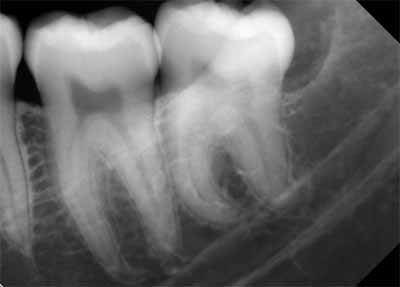

X線画像では、被写体コントラスト(X線コントラスト)の違いによって、歯を構成する3つの異なる組織を区別できます。歯冠の外側を覆うエナメル質はミネラル含有量が最も高く、そのためX線写真では最もエックス線不透過性が高いように見えます。象牙質はエナメル質よりもミネラル含有量が少ないため、エックス線不透過性が低くなります。軟組織からなる歯髄は、エックス線透過性の外観を呈します (画像3を参照)。

歯の根の周囲には、繊維性結合組織からなる歯周靭帯があります。これは、根の表面に最も近い薄いエックス線透過性の隙間として描画されます。歯周靭帯に最も近い歯槽骨は、歯槽硬線と呼ばれる薄く緻密な骨組織で構成されています。この緻密骨は、歯の根面に沿って歯槽突起の緻密骨と融合する薄いエックス線不透過領域として描かれます (画像3を参照)。

歯の発育がまだ完了していない子供や青少年では、歯列の発育段階に応じて歯の外観が変化すると考えられます。歯根の発達が不完全な歯は根尖性歯周炎に似ている可能性があるため、レントゲン写真で根尖周囲の変化を確認する際には、この点に留意することが重要です (画像4を参照)。